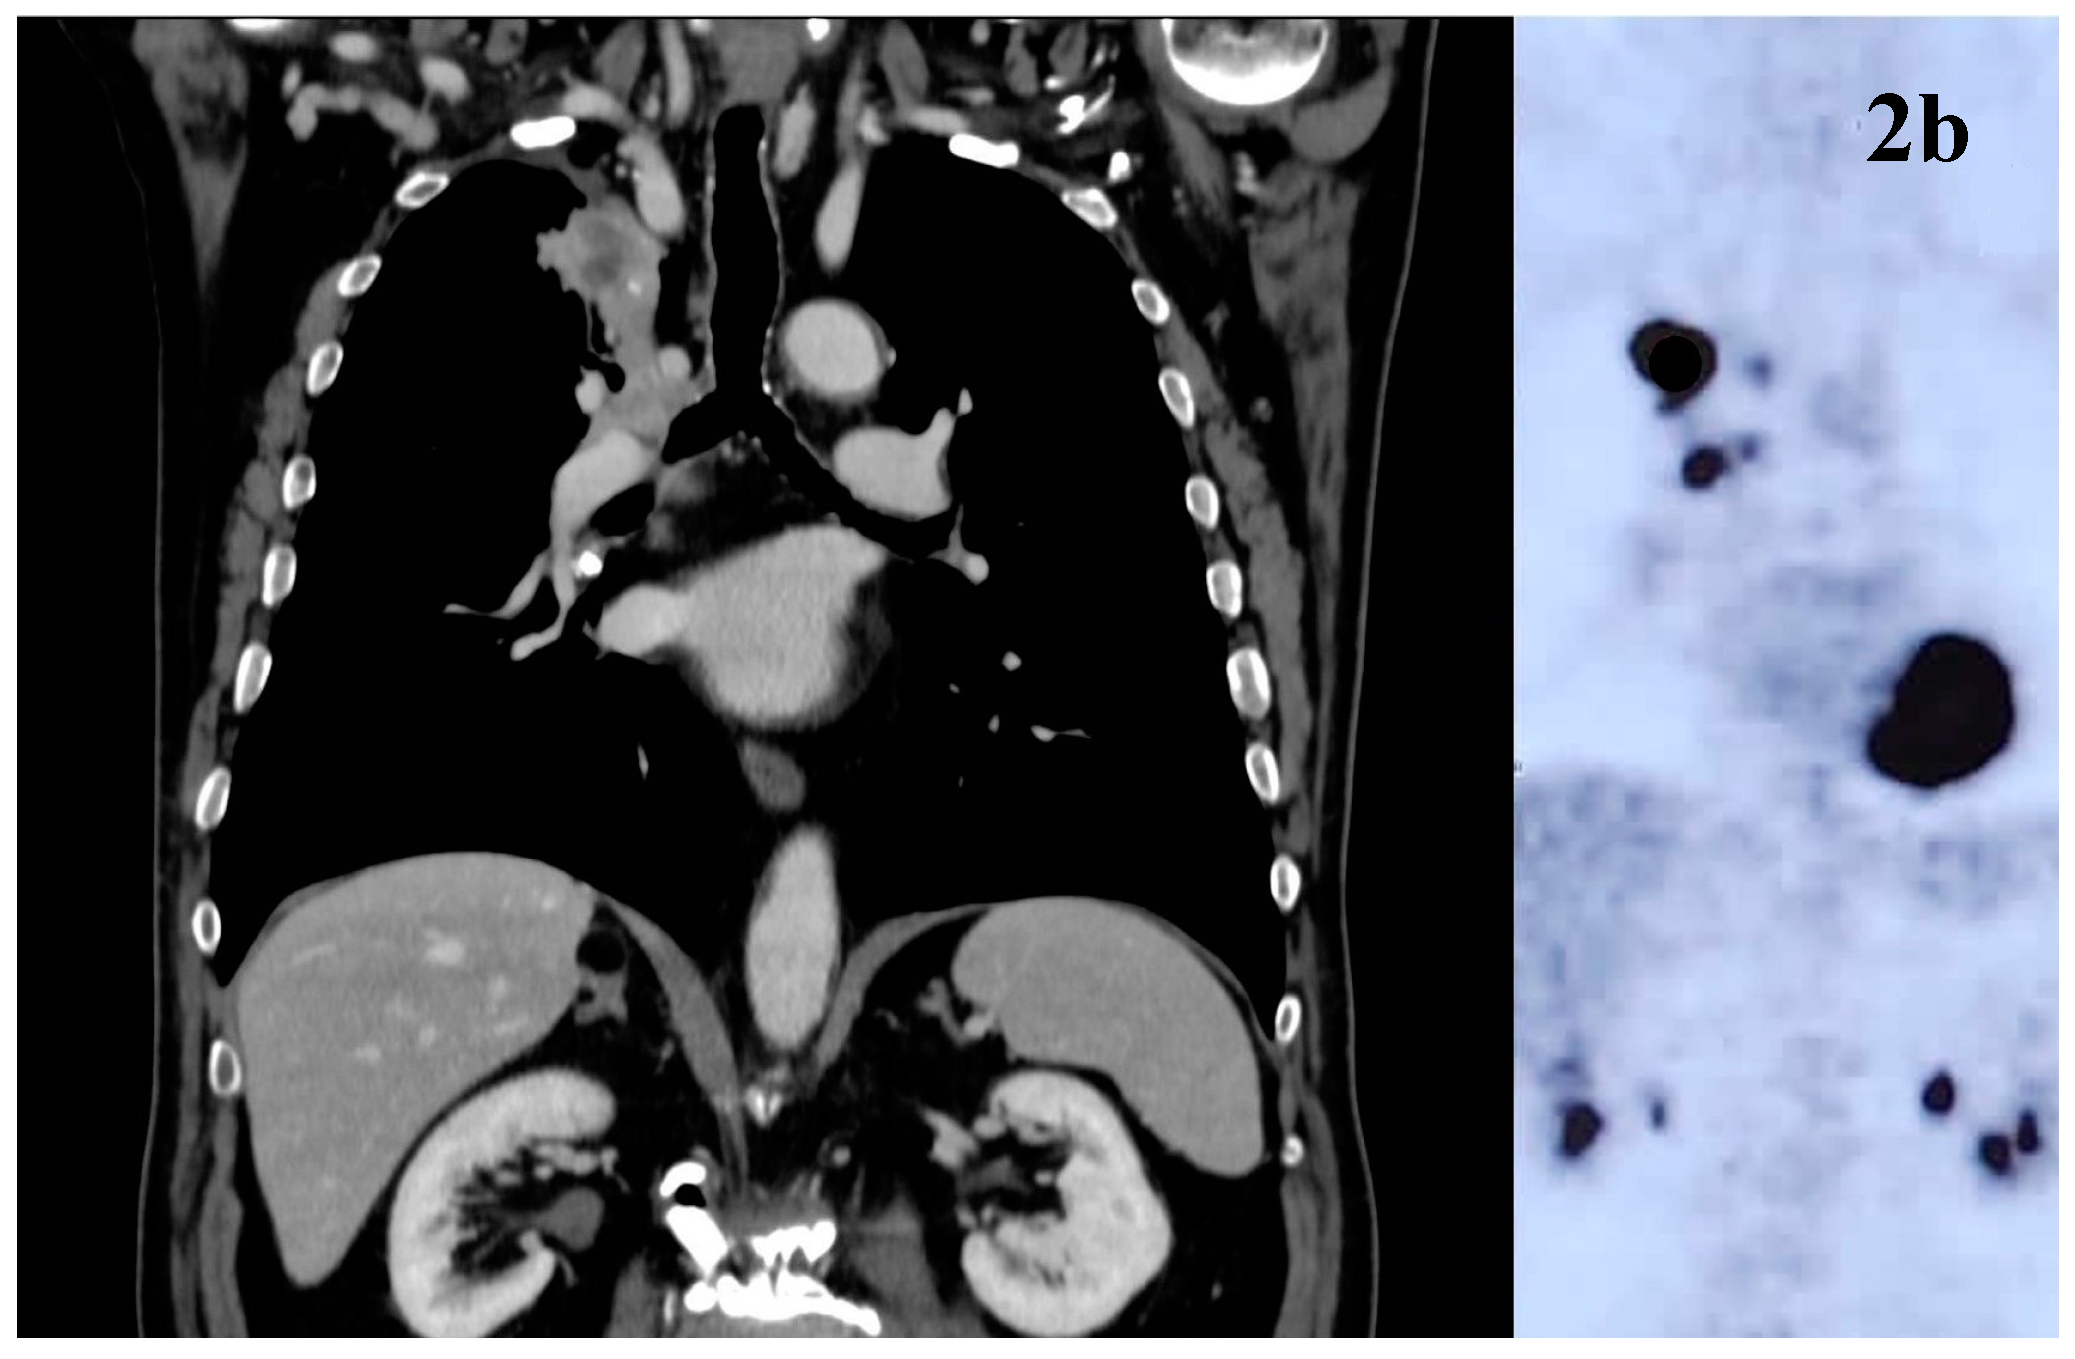

He started SRT: the frontal right lesion received 36 Gy/6 fractions and the cerebellum lesions received 24Gy/3 fractions (Figure 3a-b) [6,7,8].

In July 2022, patients received hypo-RT (45 Gy/16 fractions to lung mass and PET + nodes) (Figure 3c).

Figure 3. Radiotherapy treatment plans Legend: (a) SRT treatment plan for cerebellar lesions; (b) SRT treatment plan for frontal right lesion; (c) mediastinal hypofractionated treatment plan.